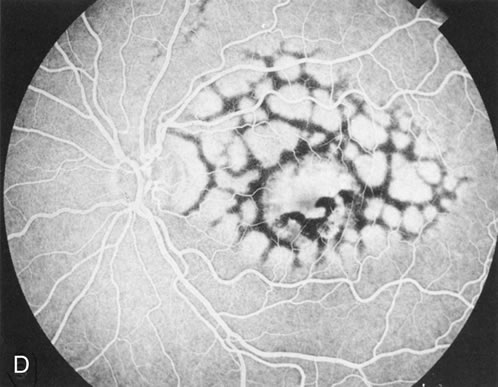

Unlike choroideremia, gyrate atrophy funduscopically has well-demarcated scalloped areas of choroidal atrophy. A hyperpigmented border separates the normal and abnormal tissue. These lesions begin as isolated areas in the midperiphery, which then merge to form a garland wreath, with progression peripherally and centrally, sparing only the macula.

FA demonstrates the sharp demarcation between normal and abnormal tissue, the former showing normal background fluorescence, the latter atrophy of the choriocapillaris (Fig. 5). Thus, the normal choriocapillaris background fluorescence in the early stages of gyrate atrophy is in contradistinction to the diffuse choriocapillaris atrophy in the early stages of choroideremia.

Fig. 5. Gyrate atrophy. The areas of choroidal atrophy (A) show choriocapillaris atrophy on the angiogram. (B) Adjacent areas of normal-appearing retina have a normal background choroidal flush.